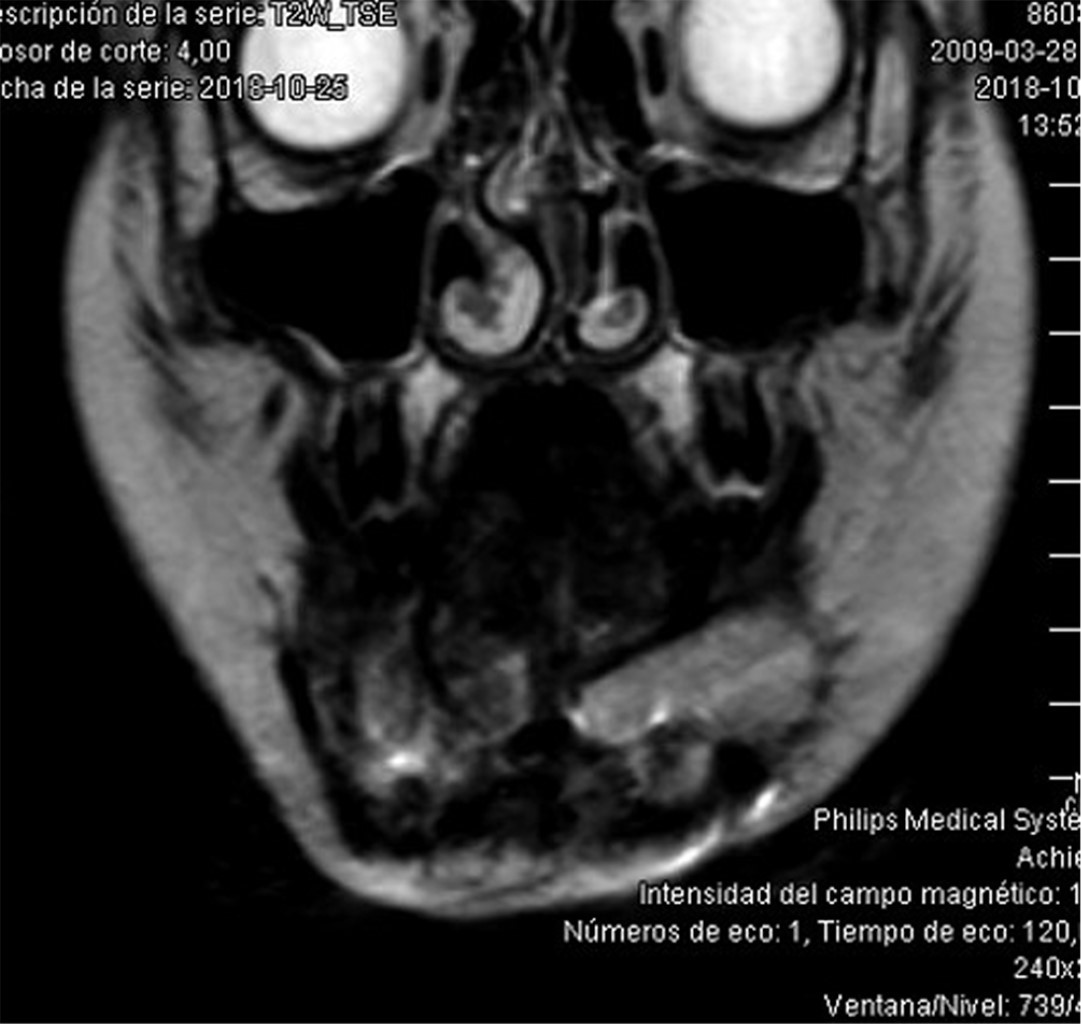

Introduction: Oral cavity squamous cell carcinoma is a frequent entity in adult malignant head and neck pathology; however, it is extremely rare in pediatric age. The treatment and reconstruction of pediatric patients is a challenge due to its high complexity and the few cases described to date in the literature. Material and methods: A clinical case of mandibular squamous cell carcinoma in a pediatric patient is presented. Diagnosis is made by histopathological study and radiological tests, and a virtual planning for mandibular reconstruction is performed. A review of the literature is performed since it is a rare entity. Results: A 9-year-old male of Asian origin came to our office for clinical symptoms of suppuration in the left mandibular region close to the first definitive molar, of approximately 2 months of evolution. A biopsy was performed with an anatomopathological result of squamous cell carcinoma. The case was presented to the Head and Neck Tumors Committee and surgical treatment was decided: left segmental mandibulectomy with oncologic safety margins, left anterolateral functional cervical dissection and reconstruction with microvascularized fibula flap fixed with titanium rod. Cutting guides and virtual planning were used. At 24 months postoperative follow-up there was no locoregional or distant recurrence. Conclusions: Oral cavity squamous cell carcinoma in pediatric age has a low incidence, requiring optimal management and reconstruction. The fibula flap could be the most indicated option for mandibular reconstruction in children. The preservation of the mandibular condyle could favor the mandibular growth of the patient during development.

Figure 4